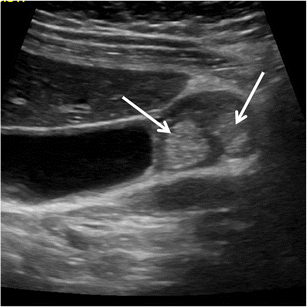

Focal intramural calcifications (Fig. 14) are virtually pathognomonic for GA. Unfortunately, GA shows intramural calcifications only in a minority of the cases.

Fig. 14

CT of gallbladder adenomyomatosis: intramural calcifications. CT accurately depicts intramural calcifications (arrows) that may develop within Rokitansky–Aschoff sinuses and which are pathognomonic for gallbladder adenomyomatosis